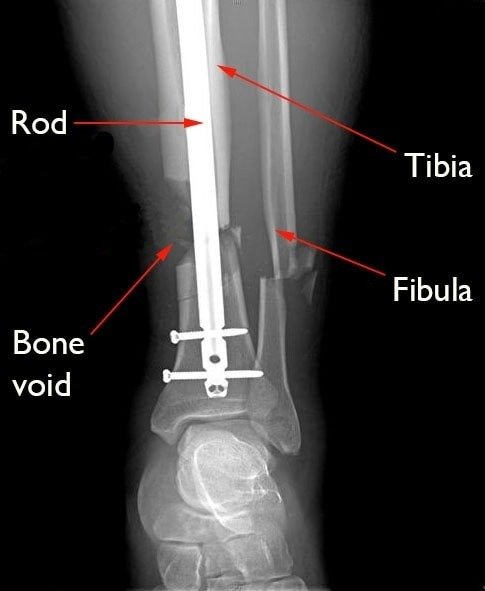

Bone healing is a natural biological process that restores bone strength and structure after a fracture or surgical procedure. However, post-surgical healing depends on several factors—such as the type of surgery, the severity of the fracture, age, bone density, and overall health.

- Medical Supervision: Regular follow-ups ensure the surgical site heals correctly and that no infection or hardware issue arises.